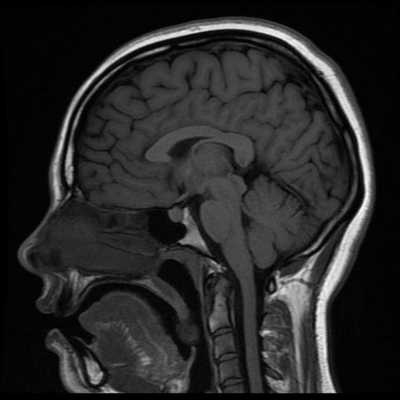

Как выглядит снимок МРТ головного мозга

Классический пример МРТ снимков головного мозга показан на рисунках ниже. Магнитно-резонансная томография выполняется в поперечной (или аксиальной - рисунок снизу) и продольной (или сагиттальной — рисунок сверху) плоскостях.

Исследование выполняется в нескольких режимах. Основные из них Т1 и Т2. Изображения, полученные в данных режимах, часто также называют Т1-взвешенными или Т2-взвешенными снимками. Изображения, показанные выше, сделаны в Т1-режиме.

Главное отличие этих режимов - в том, как на снимках отображается жидкость и воздух. В Т1 режиме ткани, содержащие большое количество воды, имеют более темную окраску, в то время как в Т2 режиме они яркие, светлые. Это легко понять, посмотрев на снимки выше - глазные яблоки визуализируются в виде светлых парных округлых образований с одной стороны яркие и светлые, с другой - темные. Следовательно, снимок справа сделан в Т1 режиме, снимок слева - в Т2. Также существует разница в том, как в этих режимах отображается серое вещество головного мозга. В Т2 режиме оно светлее, чем белое вещество.